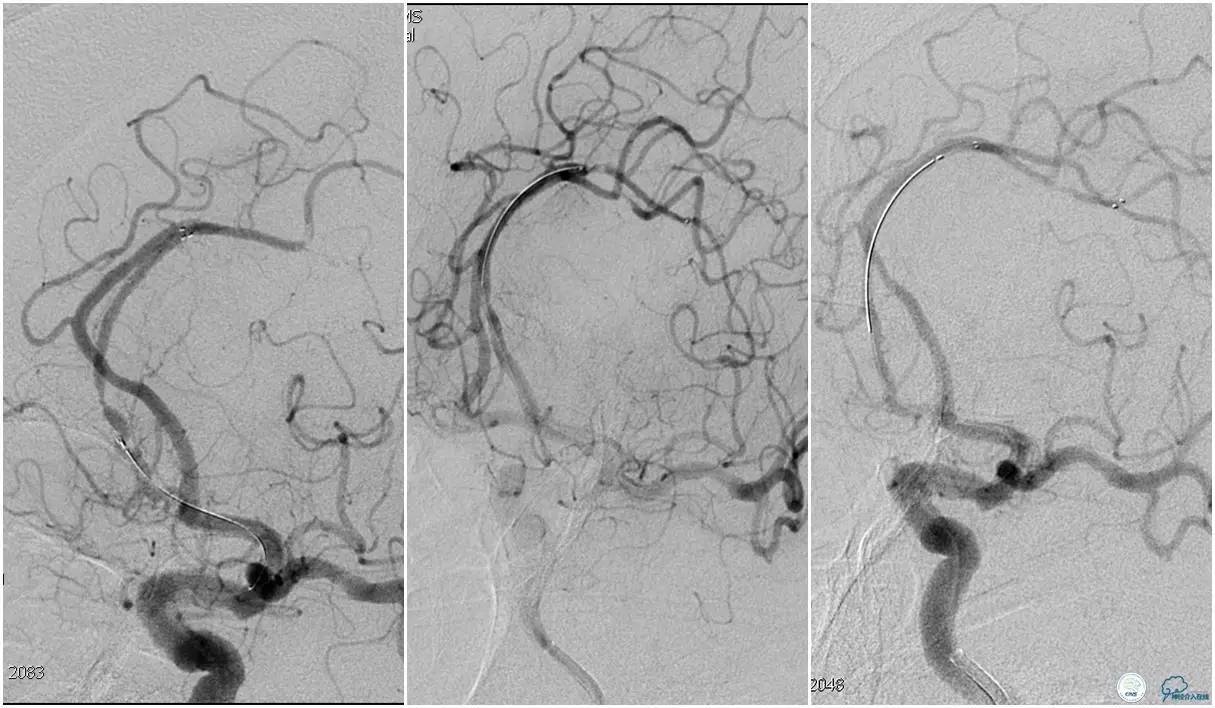

12:35穿刺成功,TOT 185min。3型主动脉弓,右侧颈内动脉起始部狭窄70%,右侧大脑前动脉A1段未显影。

双侧大脑前动脉A4段闭塞,右侧大脑前动脉由左侧大脑前动脉经前交通动脉代偿供血。

6F Envoy置于颈内动脉C3段,选用Solitaire-FR 4*20mm支架释放于右侧大脑前动脉,完全覆盖血栓。

6F Envoy置于左侧颈内动脉C3段,选用Solitaire-FR 4*20mm支架释放于右侧大脑前动脉取栓1次,血流达TICI 2b。

Solitaire-FR 4*20mm支架释放于左侧大脑前动脉取栓1次,取出少许血栓重复造影左侧大脑前动脉胼周动脉开口后,右侧大脑前动脉A2段以远未显影,考虑栓子逃逸。

选用Solitaire-FR 4*20mm支架分别于右侧大脑前动脉A2-A3段,左侧胼周动脉,右侧胼周动脉取栓3次。

双侧大脑前动脉完全显影,TICI 3级,TOR 261min。